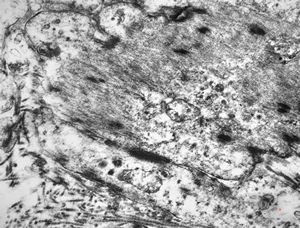

M,22y. | normal bronchial epithelium